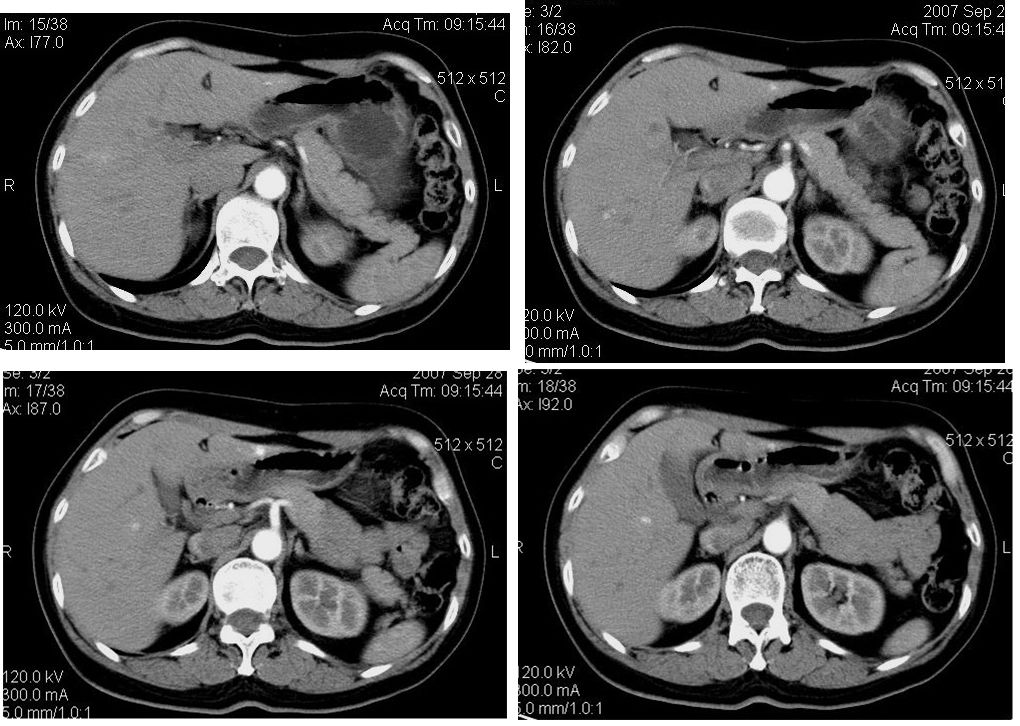

患者,女,65岁,住院准备甲状腺腺瘤用术,术前常规发现肝脏占位,ct增强扫描。

平扫

动脉期

门脉期

延迟扫描